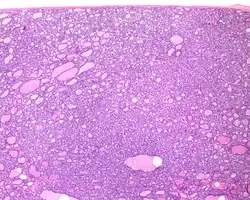

1) Encapsulated or partially encapsulated. The tumors are usually very well delimited or circumscribed, with the majority encapsulated, surrounded by a well formed fibrous connective tissue capsule.

2) Complete absence of invasion of any kind in a tumor that has been thoroughly and carefully evaluated with the whole capsule of the lesion sampled.

3) Predominantly follicular pattern of growth. Papillary structures should not be present. Further, solid, insular, or trabecular architecture must be <30% of the overall tumor for this category to still apply. Colloid (the material that thyroid follicular cells create) is easily identified throughout.

- ^ Image by Mikael Häggström, MD. Reference for findings: Rachel Jug, M.B.B.Ch., B.A.O., David Poller, M.D., Xiaoyin "Sara" Jiang, M.D. "NIFTP". Pathology Outlines.